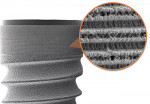

Organized roughened surfaces of specific dimensions have been developed to selectively influence fibroblast and osteoblast activity and growth patterns through contact guidance.8 These 8-µm to 12-µm grooves (Laser-Lok® microchannels, BioHorizons, www.biohorizons.com) are designed to provide a functional attachment surface for both bone and connective tissue (Figure 1 and Figure 2). This nano feature topography also directly affects the rate and amount of osteogenesis.9,10 The goal of this microengineered design is to provide long-term crestal bone and soft tissue stability. Figure 3 demonstrates the 11-year follow-up radiographic appearance of the first Laser-Lok implant.